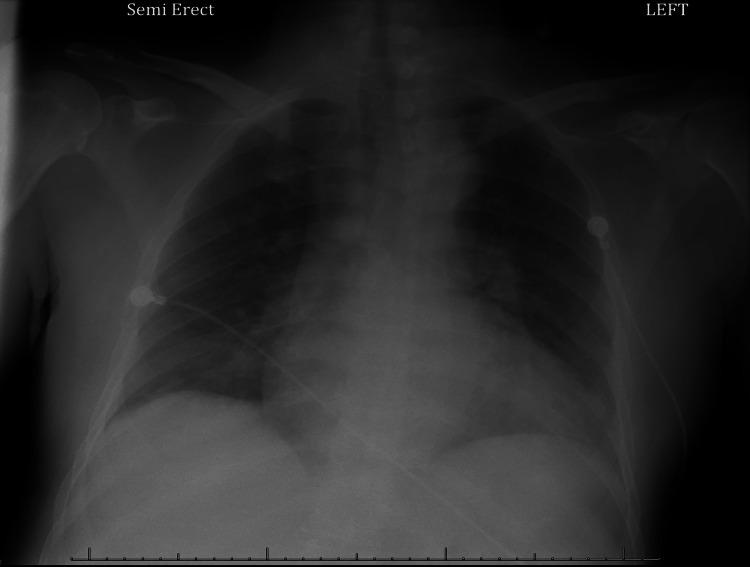

Schizophrenia is a chronic psychiatric condition that can contribute to delays in the diagnosis and treatment of health conditions. Factors like poor judgment, decreased medical literacy, cognitive barriers, and delayed seeking of therapy can result in worse outcomes of the disease. Acute gangrenous cholecystitis is a severe complication of acute cholecystitis, requiring immediate surgical intervention. We present the case of a 54-year-old Spanish-speaking male with schizophrenia who presented with seven days of progressively worsening right upper quadrant (RUQ) pain, as well as associated nausea and postprandial emesis. The patient also reported having been recently discharged from an Emergency Department (ED) on an antibiotic regimen after presenting with the same chief complaint. Further evaluation showed laboratory findings of leukocytosis (22.3 × 10³ cells/µL) and a computed tomography (CT) of the abdomen and pelvis with findings consistent with acute cholecystitis, with a possible gangrenous component. This case sheds light on the impact of psychiatric disorders on the treatment of disease. Stigmatized psychiatric comorbidities, including schizophrenia, can lead to worsened outcomes and an increased risk of life-threatening complications due to delayed initiation of proper treatment protocols. Increased awareness, identification of biases, and practiced protocols for disease management should be upheld in patients with mental illness to prevent complications.

精神分裂症是一种慢性精神疾病,可能导致健康状况诊断和治疗的延迟。判断力差、医学素养下降、认知障碍以及延迟寻求治疗等因素可能导致疾病预后更差。急性坏疽性胆囊炎是急性胆囊炎的一种严重并发症,需要立即进行手术干预。我们报告一例54岁讲西班牙语的男性精神分裂症患者,他出现右上腹(RUQ)疼痛进行性加重7天,伴有恶心和餐后呕吐。患者还报告,在因相同主诉就诊后,最近刚从急诊科出院并接受抗生素治疗。进一步评估显示白细胞增多(22.3×10³个细胞/µL),腹部和骨盆计算机断层扫描(CT)结果与急性胆囊炎一致,可能存在坏疽成分。该病例揭示了精神疾病对疾病治疗的影响。包括精神分裂症在内的受歧视的精神疾病合并症,可能由于未能及时启动适当治疗方案而导致预后恶化和危及生命并发症的风险增加。对于患有精神疾病的患者,应提高认识、识别偏见并实施疾病管理方案,以预防并发症。